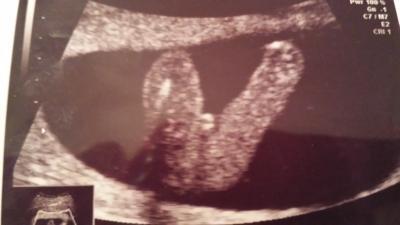

Heute bei 16+1.was meint ihr?Hab ein Outing was über 90%ist. ..trau dem ganzen aber noch nicht...lg

Bild zu Junge oder Mädchen was meint ihr? - Schwanger - wer noch? Rund um die Schwangerschaft

Ich persönlich würde Mädchen sagen ..ich habe 2 Jungs und ein Mädchen und sieht eher wie Mädchen aus

Sieht nach Junge aus.

Na,das Zimmer würde ich nicht rosa streichen...frage mich gerade,wie man da ein Mädchen reininterpretieren kann . Ich sehe da Hoden ,warte mal den nächsten Ultraschall ab,um ganz sicher zu gehen...

Also ich habe 4 Jungs und das ist definitiv KEIN Junge

das ist für mich eindeutig ein Mädchen!!!

hmmmm... ich habe 3 Söhne - das sah anders aus. Jetzt bekommen wir eine Tochter - aber auch das sieht anders aus, mich irritiert, dass die "Schamlippen" nicht parallel zu den Beinen verlaufen sondern so quer... grübel... ich würd lieber noch nicht rosa streichen...

ich seh da gar nichts, kann nämlich auch die nabelschnur sein....... also tippe ich eher auf mädchen